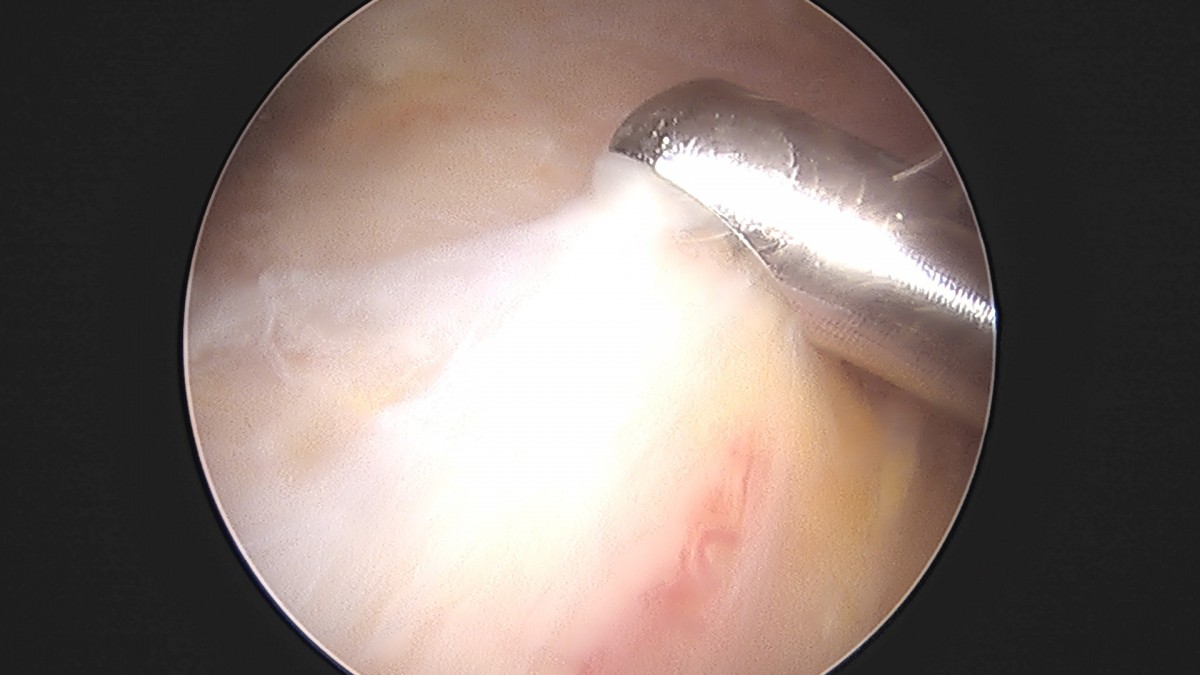

이재상원장님 어깨 견봉하 감압술 및 관절낭 이완술 양명O 환자

작성자 최고관리자 댓글 0건 조회 788회 작성일 25-09-16 15:33